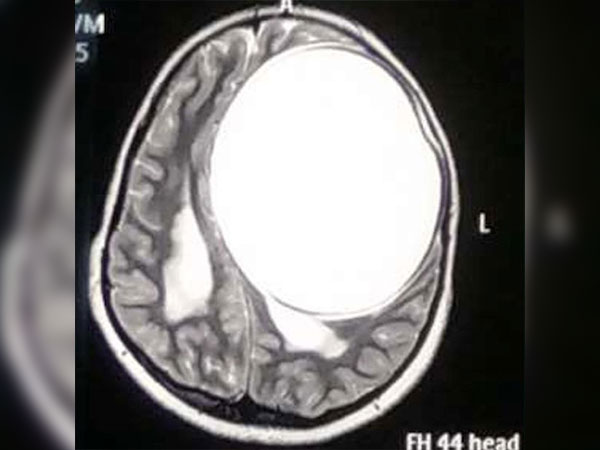

மயக்க நிலையில் மருத்துவமனைக்கு அழைத்து வரப்பட்ட லீமாவுக்கு உரிய சிகிச்சைகள் கொடுக்கப்பட்டன. அவளுடைய மூளை நரம்பு மண்டலத்தை பரிசோதித்த போது தான் மருத்துவரும் அதிர்ந்து போனார். ஏனெனில் லீமாவின் மூளைக்குள் நூற்றுக்கான வெள்ளை நிறப் புள்ளிகள் இருப்பது கண்டறியப்பட்டது. அது என்னவென்று சோதித்துப் பார்த்தார்கள். அது என்னவென்று தெரியுமா? ஆம் அவ்வளவும் நாடாப் புழுக்களின் முட்டைகள்.

மருத்துவமனைக்கு அழைத்து வரும்போதே லீமாவுக்கு ரத்த அழுத்தமும் அதிகமாகவே இருந்தது. அதனால் மிக கவனமாக மருத்துவர்கள் சிகிச்சை அளித்தனர். நாடாப் புழுக்கள் கொடுத்த அழுத்தமானது மூளையை பாதித்ததோடு மூளையின் செயல்பாட்டையும் நிறுத்திவிட்டது. அதற்காக முதலில் மூளையில் அழுத்தம் குறைவதற்கான மருந்துகள் கொடுக்கப்பட்டன. பின்னர் கட்டி போல இருந்த முட்டைகளைக் கொல்வதற்கு மருந்துகள் கொடுக்கப்பட்டன.

மூளையில் உள்ள நாடாப்புழுக்களின் முட்டைகளை அழிப்பதற்கு மருந்து கொடுப்பது இன்னும் கூடுதல் சிக்கல்களையே கொடுக்கும். ஏனென்றால் அந்த சமயங்களில் மூளைக்கு அழுத்தங்களையும் அதிகரிக்கச் செய்யும். மூளையில் உள்ள நாடாப்புழுக்களை அழிக்க மருந்துகள் கொடுக்கப்பட்டாலும் கூட, முட்டைகளின் எண்ணிக்கை அதிகமாகிக் கொண்டே தான் இருக்கும்.